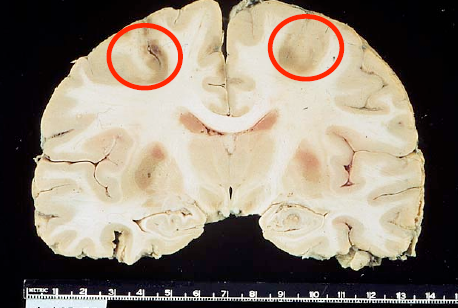

15 year old presents with first seizure. What is the cause of this pathology? Is there normal tissue?

AVM

Located in cortex

Composed of both large arteries (open arrow) and veins (solid arrow) without

intervening capillaries.

Between vessels there is gliotic nonfunctional hemosiderin stained tissue (circle).